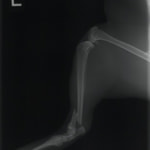

ペルシャ猫 11ヶ月齢 雄

他院にて左大腿骨遠位の成長板骨折(salter-harrisⅠ型)が認められており、治療相談を目的として来院。当院にて、キルシュナーワイヤーを用いたピンニングにより骨折部位の整復を行いました。術後の経過は良好で、現在も経過観察中です。

術前レントゲン